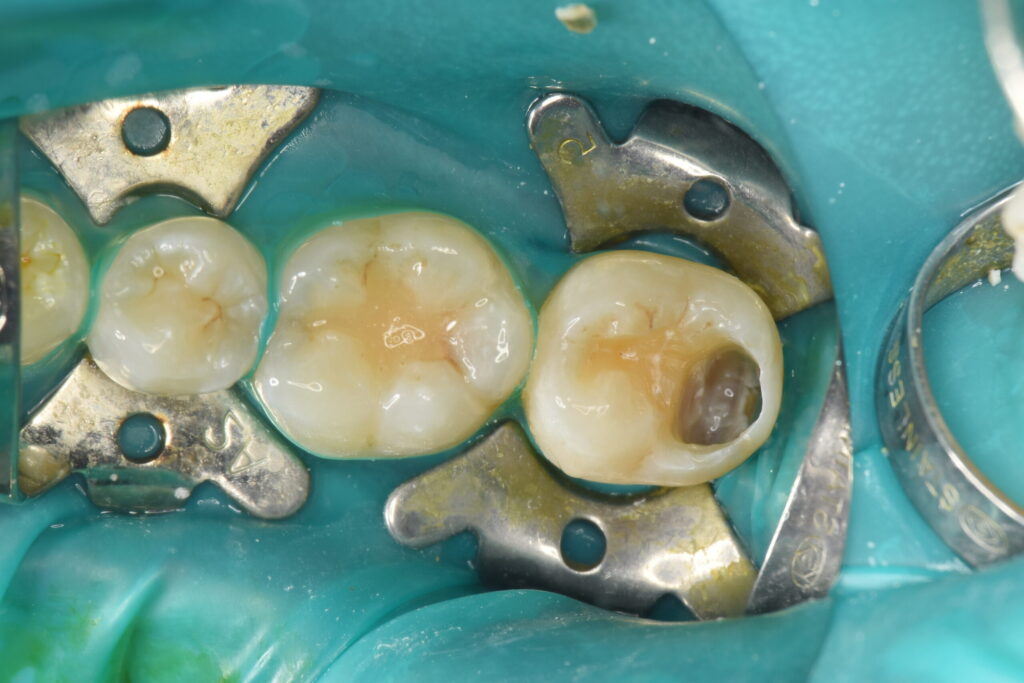

ラバーダム防湿を行い清潔な状態を確保し虫歯を少しずつ除去していきます。

青く染まっているのが虫歯です、もう少し虫歯を除去していきます。